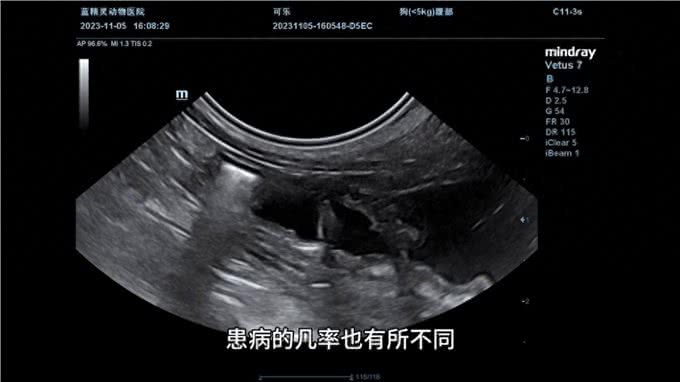

宠物子宫蓄脓是一种常见的生殖道疾病,通常在狗狗身上比较常见。根据狗狗的品种和年龄等因素,患病的几率也有所不同。子宫蓄脓是指狗狗的子宫内出现脓液积聚,通常分为闭锁型和开放型两种类型。

如果狗狗出现子宫蓄脓的症状,需要及时带它去医院做b超检查,确认是否患有子宫方面的问题。如果确诊为子宫蓄脓,治疗方式通常为切除子宫和卵巢,因为输液打针或冲洗的效果都不好,如果不及时治疗可能会引发败血症、酸中毒和肾后性衰竭等严重后果。